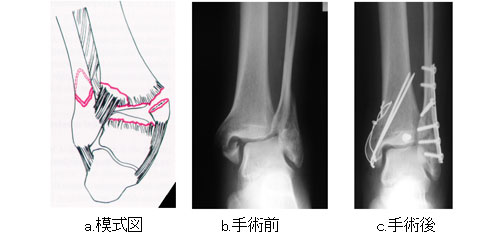

足関節骨折 一般社団法人 日本骨折治療学会 骨折の解説

足関節骨折 一般社団法人 日本骨折治療学会 骨折の解説

足関節骨折 一般社団法人 日本骨折治療学会 骨折の解説

足関節骨折 一般社団法人 日本骨折治療学会 骨折の解説

治療例 下肢 膝 足 保谷 骨折治療 川崎接骨院 交通事故の治療など